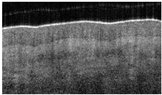

Hair-bearing skin papillary pattern. (a) Healthy skin, (b) healthy skin en-face view, (c) superficial burn, (d) superficial burn en-face view partially damaged, (e) deep burn, and (f) deep burn en-face view totally disrupted papillary pattern.

The en-face view of hair-bearing skin displays a characteristic pattern of small, dark spots at the level of the papillary dermis (Figure 3b). These spots represent openings in the dermal matrix for hair and the papillary vascular plexus. These spots are regularly spaced in the papillary dermis (Figure 3b), and the loss of this pattern (Figure 3f) indicated a deeper dermal wound that would eventually require a skin graft. We only observed this pattern in hear-bearing skin. The partial (Figure 3d) or complete disruption (Figure 3f) of this pattern was observed, and a score of 1 or 2 was assigned.